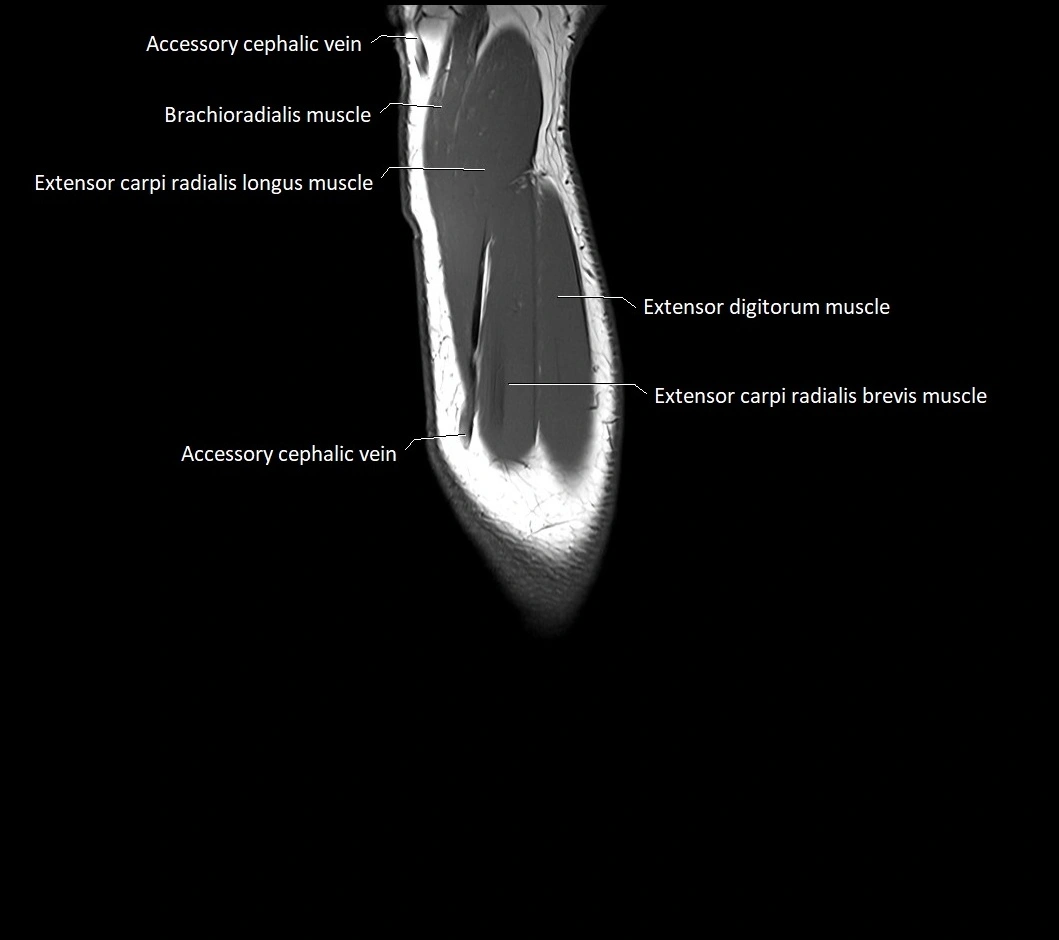

MRI images

image